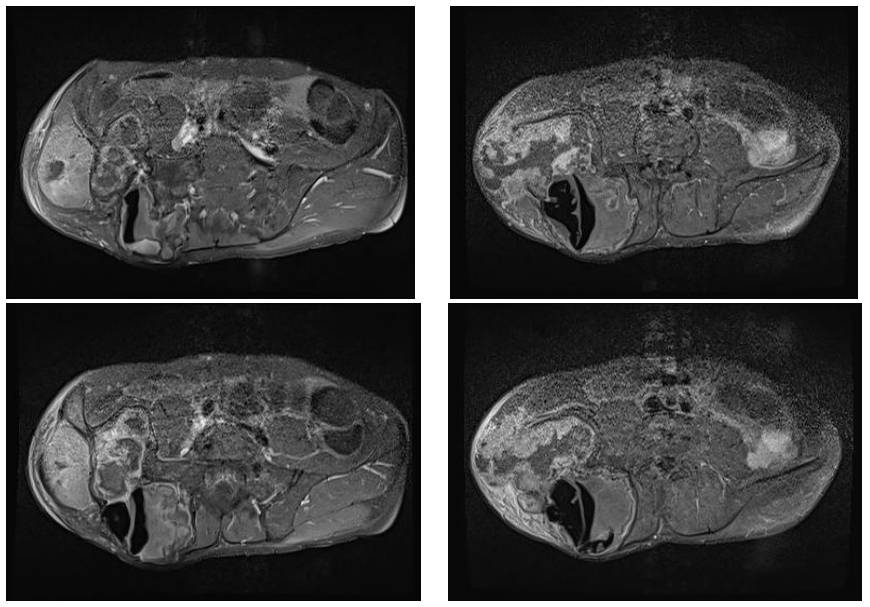

Ameliyat Öncesi: Tomografide sağ ilaik kanatda genişleme düzensizlik harabiyet ve sement varlığı görülmekte

Ameliyat Öncesi: PET_CT’de sağ ilaik kanat dış kısımda artmış yoğun aktivite görülmekte